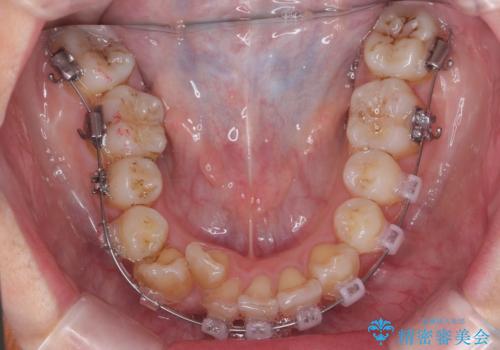

- ワイヤー矯正

上の歯列を後ろに下げるのに、矯正用ミニスクリューを使用しています(インプラント矯正)

また、上の前歯を下げるために抜歯という選択肢もありましたが、前歯の大きさを若干小さく削り、奥歯を後ろに下げるというのを試みて、難しいようなら抜歯という形で進めました。

結果、遠心移動もスムーズに進み大きく前歯を下げることができました。